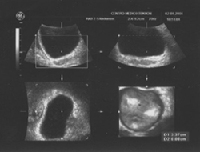

La biopsia hepática obtenida por punción ecodirigida se considera el método de elección en el diagnóstico y estadificación de la cirrosis hepática.

La ecografía permite poner de manifiesto la existencia de hepatocarcinoma (cáncer hepático), es muy útil en el diagnóstico de esteatosis (grasa) hepática, y de cirrosis descompensada.

Se trata de una reconstrucción en tres dimensiones y por lo tanto en tres planos ortogonales (3-D), con detalles anatómicos y patológicos más precisos, incluso vasculares (Angio-Doppler Color 3-D). Se utiliza en:

- Cálculo de volúmenes (Vesicula Biliar, Estómago, Quistes y Tumores).

- Estudio de la arquitectura vascular de los tumores.

- Biopsia dirigida por ecografía 3-D.

- Ayuda a la Ecografía Intervencionista.